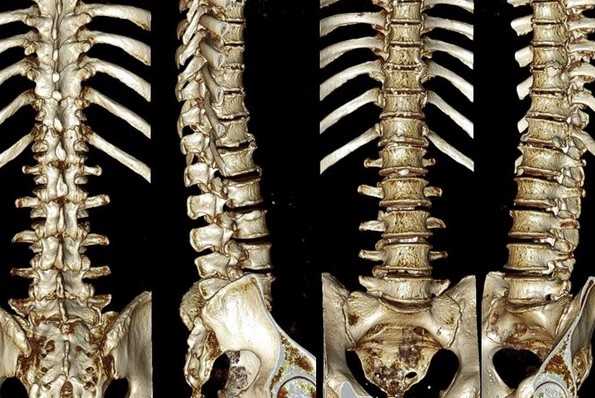

Сколиоз позвоночника на снимках КТ

КТ позвоночника что показывает

Компьютерная томография является одним из наиболее популярных видов изучения костных и хрящевых анатомических образований. Сканирование проводят с помощью рентгеновского излучения. Твердые ткани организма активно поглощают ионизирующие потоки, обеспечивая возможность детальной визуализации строения внутренних структур. КТ позвоночника проводят для определения состояния костных и хрящевых элементов, окружающих тканей, кровеносных сосудов.

В результате компьютерной томографии получают серию послойных изображений рассматриваемой зоны. Монохромные фотографии обладают высоким разрешением. В отличие от рентгенографии на снимках отсутствуют дефекты и тени от расположенных рядом структур. Изменение плоскости при реконструкции изображений позволяет тщательно изучить анатомические образования. Преимуществом КТ является возможность создания 3D-модели позвоночника.

Компьютерная томография позвоночника показывает малейшие нарушения строения и функциональности суставных элементов. Трехмерное изображение при подготовке к хирургическому вмешательству позволяет локализовать патологический процесс, уточнить объем предстоящей операции.

Трехмерная реконструкция при КТ